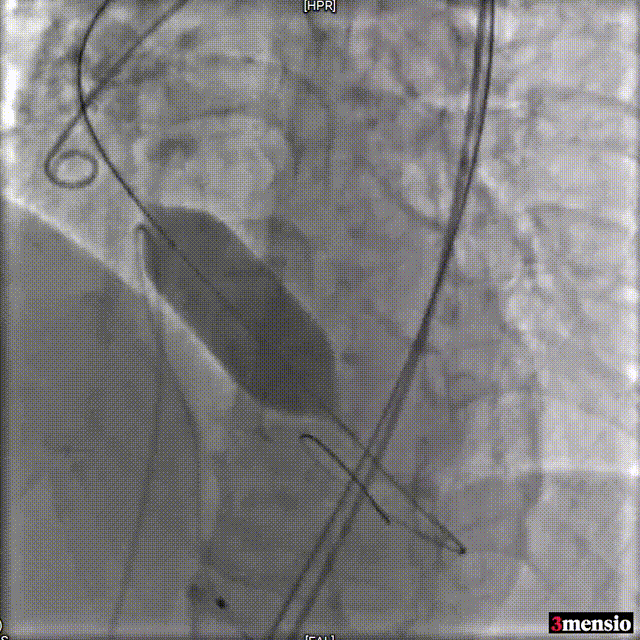

Snare辅助输送系统过弓

瓣膜定位

释放瓣膜